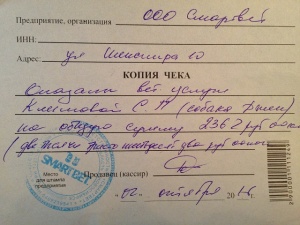

– прием дерматолога, врач Аверьянова Александра Михайловна, клиника АС Вет (400 руб.), вет диета Hills t/d для снятия налета с зубов (1979 руб.), Милпразон (антигельминтный препарат) 400 руб. (скидка на сумму чека 15%) (чек 3, копия чека 3, лист назначений – документ 3) – 2362 руб.

– прием дерматолога, врач Аверьянова Александра Михайловна, клиника АС Вет (400 руб.), вет диета Hills t/d для снятия налета с зубов (1979 руб.), Милпразон (антигельминтный препарат) 400 руб. (скидка на сумму чека 15%) (чек 3, копия чека 3, лист назначений – документ 3) – 2362 руб.